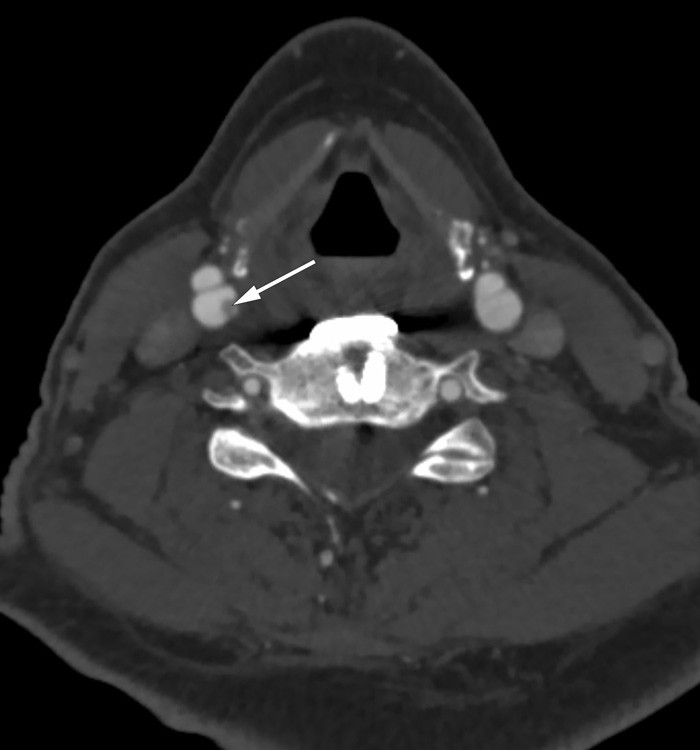

Først to år etter første hjerneinfarkt viste ny ultralydundersøkelse av høyre a. carotis interna en pendulerende, veggtilheftet masse (video) som med pulsativ bevegelse inn i lumen ga intermitterende stenose på rundt 60 % . Funnet ble også sett på CT-angiografi, som viste veggforandringer (bilde kun i nettutgaven). Ved sammenlikning av flere CT-angiografiske undersøkelser så man leieendring av carotiskar på høyre side. Veggforandringens utseende var ikke typisk for arteriosklerotiske plakk, idet det var en enslig fokal lesjon som protruderte inn i lumen med membranliknende seil (bildet).